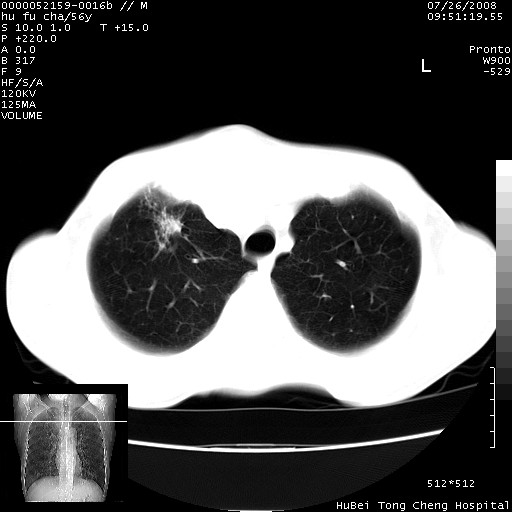

以下是引用zsl6918在2008-8-25 22:47:00的发言:[br]胸骨,胸椎及肋骨均可见多发转移表现,肝内低密度结节不除外转移。原发灶可能在右肺。双侧可见支扩表现。